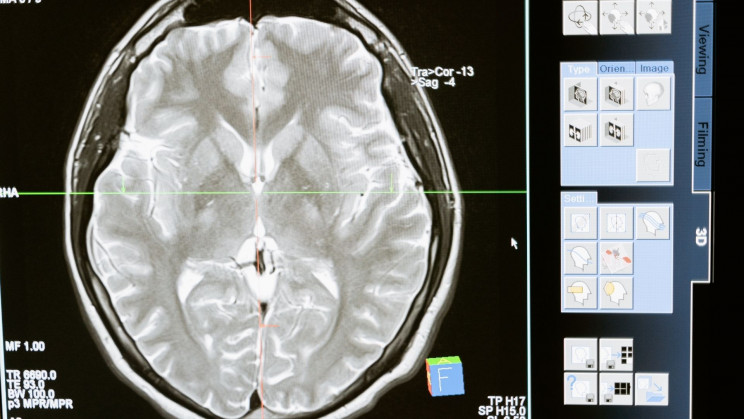

Depression, anxiety, stress, memory loss (both short-term and long-term), bipolar mood disorder, schizophrenia, hallucinations, and many other psychological ailments have been found to be connected with sleep quality and time, both directly and indirectly.

REM sleep, in particular, may play an important role in maintaining mental health. During REM (rapid eye movement) sleep, brain activity increases, your eyes dart around quickly, and your pulse, blood pressure, and breathing speed up. This is also when you do most of your dreaming. REM sleep is important for learning and memory. REM cycles are thought to hold significance for emotional well-being because during sleep they allow your brain to effectively process all of the experiences that you had during the day. Thus, the lack of sufficient REM sleep may be especially harmful to the consolidation of positive emotional content.